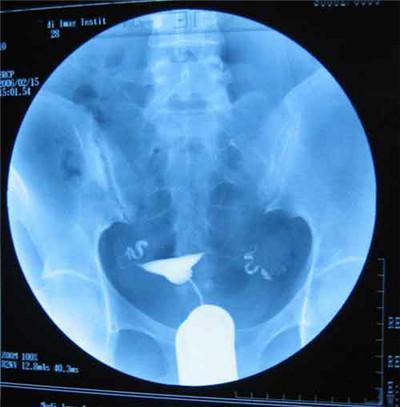

我说:“简单的说,是通过导管,向宫腔、及输卵管注入造影剂,利用X线诊断仪进行X线透视及摄片,根据造影剂在输卵管、及盆腔内的显影情况,来了解输卵管是否通畅、阻塞部位及宫腔的形态。”